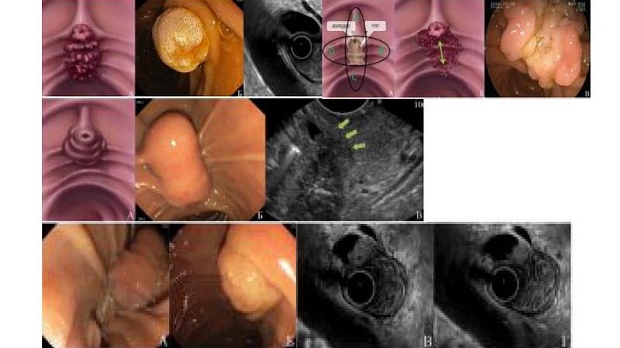

Выделяют 4 типа опухолей БСДК:

• I тип (ЕP) – экстрапапиллярный рост опухоли в пределах БСДК без распространения на протоки

• II тип (ЕPD) – также экстрапапиллярный рост опухоли, но с распространением на стенку ДПК

• III тип (ID) – внутрипротоковый рост с распространением на протоки

• IV тип (EP+ID) – смешанный тип.

В классификации мы выделяем 4 типа новообразований БСДК в зависимости от их размеров, характера роста в пределах БСДК, а также в зависимости от распространения на стенки ДПК и терминальные отделы ОЖП и ГПП.

I (EA) тип: опухоль с экстраампулярным ростом (рис. 1). Новообразование данного типа локализуется в пределах БСДК, без признаков распространения на ДПК и терминальные отделы ОЖП и ГПП. Выбор оперативного вмешательства при таком типе зависит от размеров новообразования. Наиболее эффективным эндоскопическим вмешательством при размерах опухоли менее 3 см является удаление методом резекции БСДК единым блоком. В случае если размер новообразования превышает 3 см, его следует удалять методом пофрагментной резекции БСДК.

II (ЕАD) тип: опухоль с экстраампулярным ростом и распространением на стенку ДПК (рис. 2). В зависимости от направления распространения новообразования по отношению к БСДК выделяются 5 подтипов: А — проксимальнее БСДК, В — вправо от БСДК, С — дистальнее БСДК, D — влево от БСДК, а также подтип Р, когда имеет место распространение опухоли на стенки пара- или перипапиллярного дивертикула. У новообразований II типа не отмечается внутрипротоковой инвазии. При данном типе оптимальным эндоскопическим вмешательством при размерах опухоли менее 2 см и протяженности латерально распространяющегося компонента менее 0,5 см является удаление новообразования методом резекции БСДК с резекцией слизистой ДПК единым блоком. В случае, когда размер опухоли превышает 2 см, а протяженность латерально стелящегося компонента более 0,5 см, резекцию БСДК и резекцию слизистой ДПК следует проводить пофрагментно.

III (IA) тип: опухоль с интраампулярным (внитрипротоковым) ростом (рис. 3). В зависимости от вовлечения в опухолевый процесс терминальных отделов ОЖП и ГПП новообразования данного типа разделятся на 4 подтипа: А (Ampula) — опухоль локализуется внутри БСДК и представлена исключительно интраампулярным компонентом, СBD (Common bile duct) — интраампулярная опухоль распространяется на терминальный отдел ОЖП, 3 MPD (Main pancreatic duct) — распространение на ГПП, а также подтип CBD+MPD, когда имеет место вовлечение обоих протоков. Для удаления новообразования III типа могут применяться как эндоскопические, так и хирургические вмешательства. Наиболее адекватным методом лечения новообразований типа IIIA является эндоскопическая папиллэктомия. При опухолях типа IIICBD/MPD/CBD+MPD с распространением на терминальные отделы протоков менее 1 см выполняется эндоскопическая папиллэктомия с предварительной ЭПСТ и последующей абляцией внутрипротокового компонента. При внутрипротоковом распространении опухоли более 1 см эндоскопическая операция не показана и следует рассмотреть тот или иной вид хирургического вмешательства.

IV (EA+IA): опухоль со смешанным экстра-интраампулярным ростом (рис. 4). Новообразования данного типа характеризуются экстраампулярным ростом (с или без распространения на стенки ДПК) и распространением на ампулу БСДК или терминальные отделы протоков и в целом представляют собой комбинацию I и III типов, или II и III типов. Удаление смешанных экстра-интраампулярных опухолей возможно как эндоскопическими, так и хирургическими методиками. При выполнении эндоскопических вмешательств в зависимости от размеров новообразования, распространения на стенки ДПК и терминальные отделы протоков возможно применение как пофрагментной резекции БСДК, так и папиллэктомии единым блоком, при необходимости дополненных ЭПСТ и внутропротоковой абляцией. В случаях внутрипротоковой инвазии более 1 см эндоскопические операции не оправданы, необходимо использовать хирургические методики.